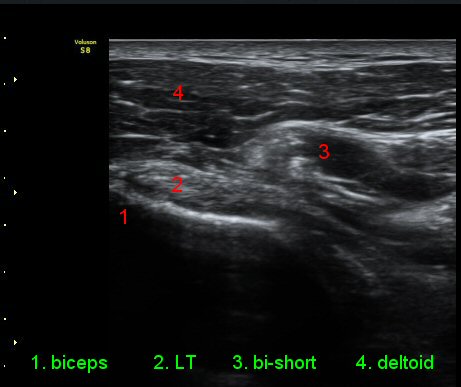

ŽÃËÀÚ¸¦ ¿À±¸µ¹±â ¾Æ·¡·Î ±æ°Ô ´ë°í °üÂûÇÏ´Ï ¿À±¸µ¹±â ¾Æ·¡, ¼ÒÈä±Ù ½ÉÃø¿¡ ¼ö¾×Àú·ù°¡

°üÂûµÇ¾î ¿À±¸µ¹±âÇÏÁ¡¾×³¶¿°À» ½Ã»çÇÑ´Ù(»çÁø 5).